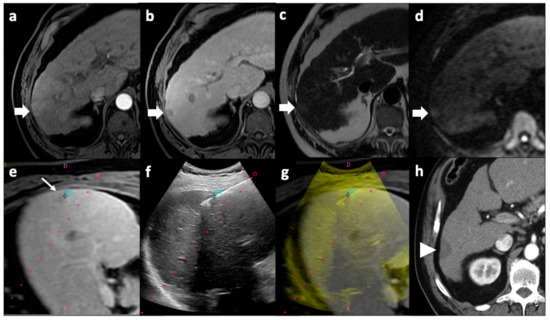

- Biondetti, P.; Fumarola, E.M.; Ierardi, A.M.; Coppola, A.; Gorga, G.; Maggi, L.; Valconi, E.; Angileri, S.A.; Carrafiello, G. Percutaneous US-Guided MWA of Small Liver HCC: Predictors of Outcome and Risk Factors for Complications from a Single Center Experience. Med. Oncol. 2020, 37, 39. [Google Scholar] [CrossRef] [PubMed]

- Patella, F.; Pesapane, F.; Fumarola, E.; Zannoni, S.; Brambillasca, P.; Emili, I.; Costa, G.; Anderson, V.; Levy, E.B.; Carrafiello, G.; et al. Assessment of the Response of Hepatocellular Carcinoma to Interventional Radiology Treatments. Futur. Oncol. 2019, 15, 1791–1804. [Google Scholar] [CrossRef] [PubMed]